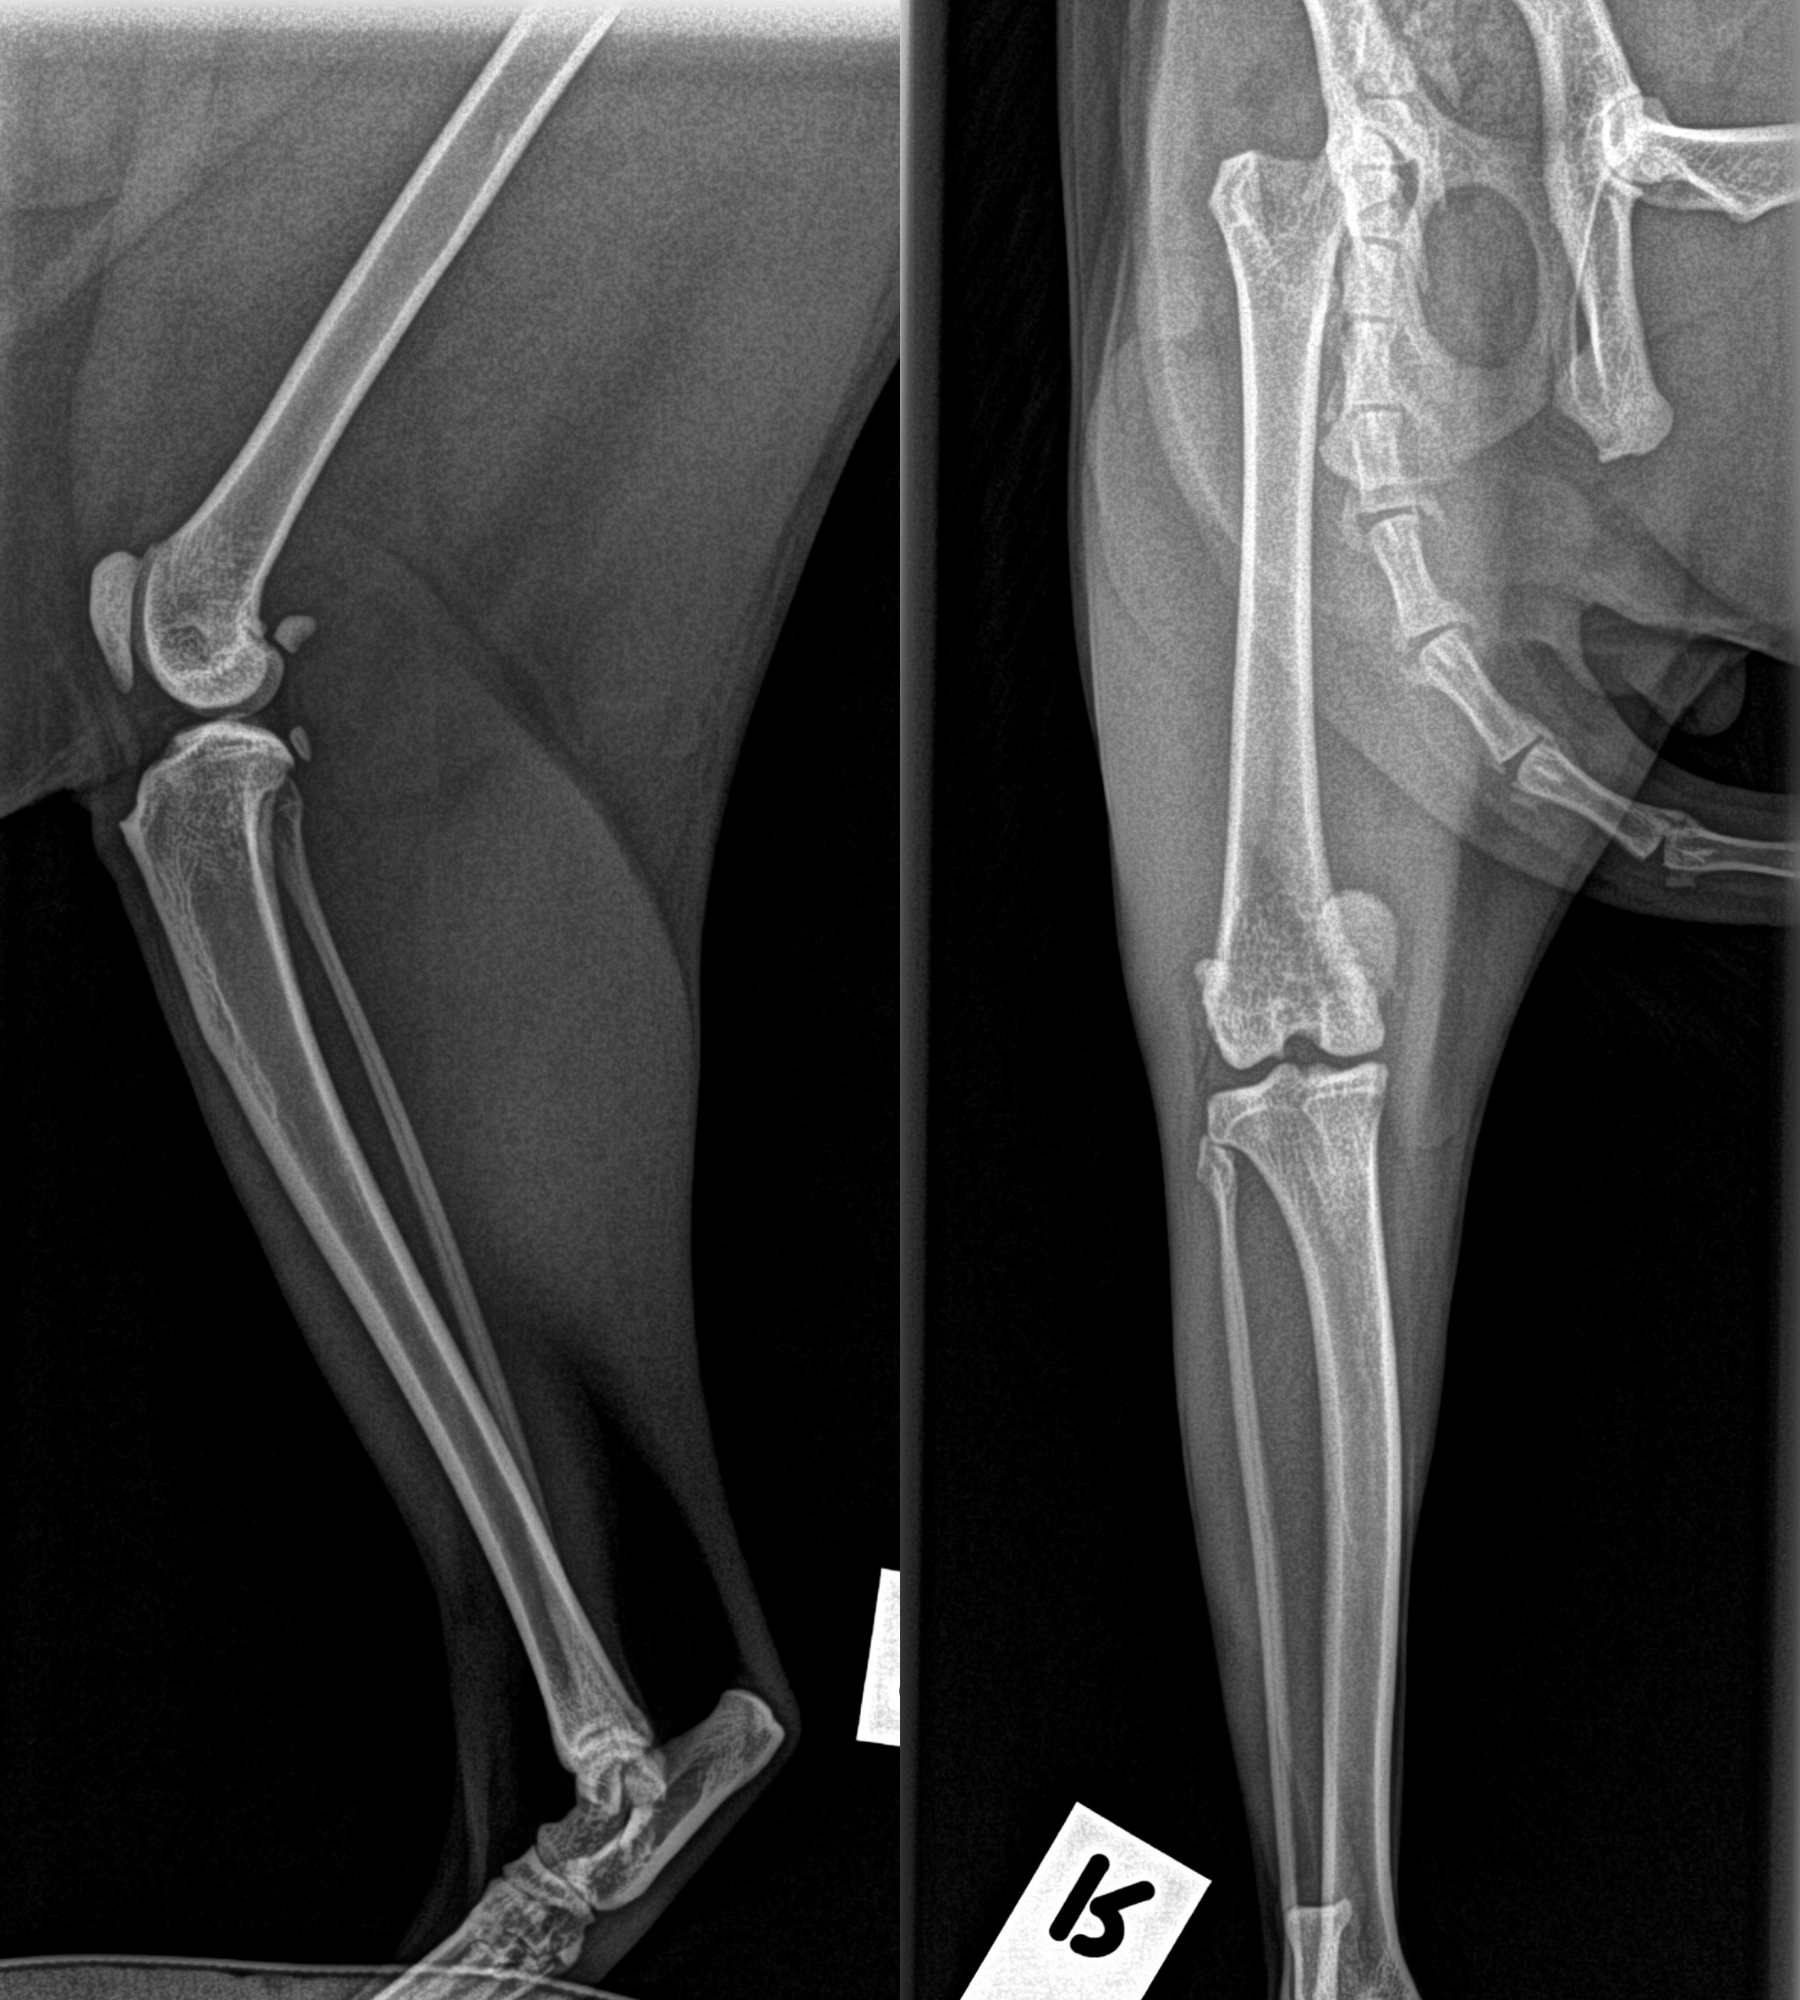

In Elrondâs case, X-rays revealed:

This combination meant his kneecap could easily slip out of place  causing pain, instability, and that tell-tale skipping limp.

To fix the problem, Elrond underwent medial luxating patella repair surgery performed by Dr Steve Pryor.